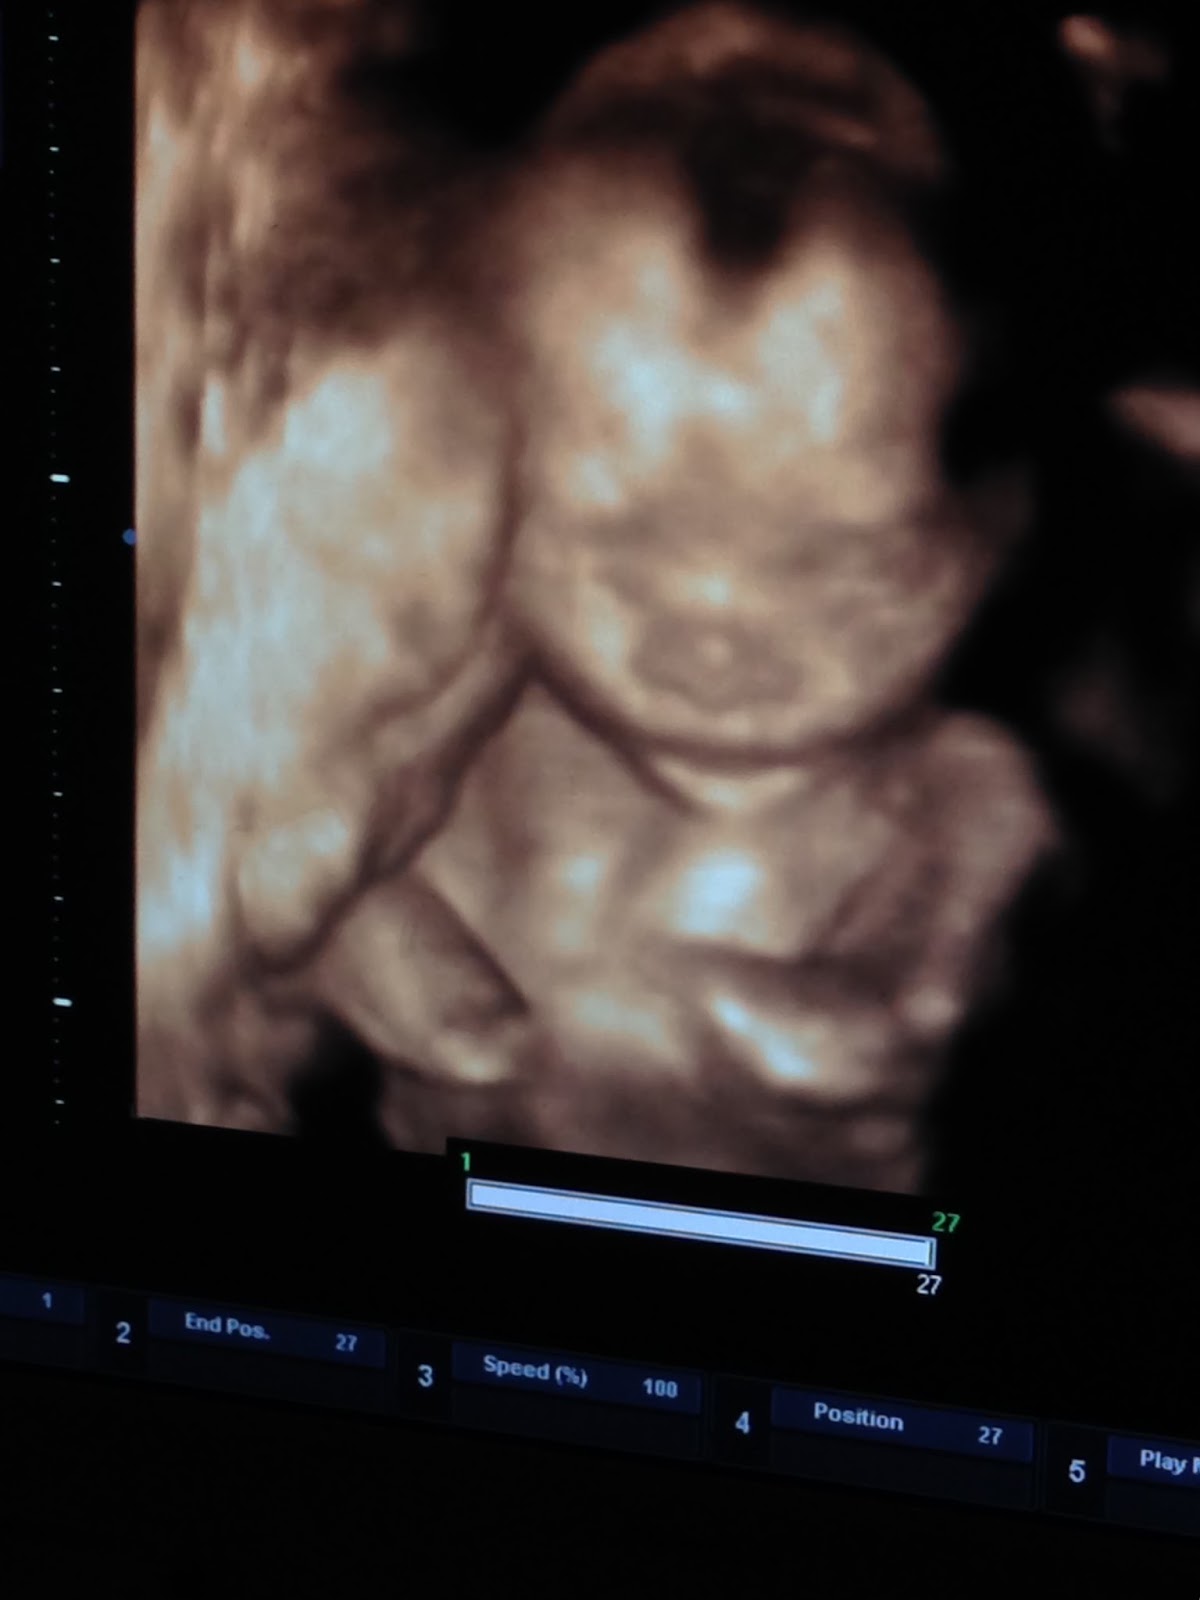

This is the best shot we got! You actually measured a few days ahead of schedule, so we got your official due date of March 31, 2015!